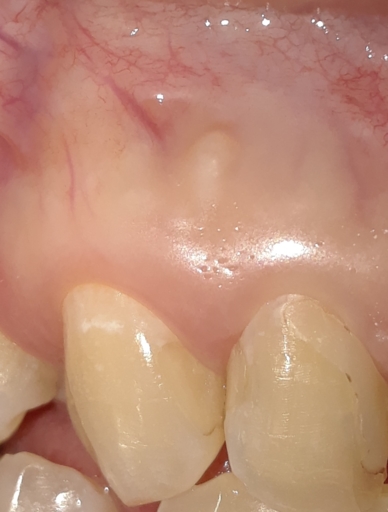

Have had root canal on teeth 8 and 7. still infection and gum boils every few months and pain.

I have had root canals on teeth 8 and 7. This was a two years back on the one tooth and an year and a half on the other about...They want to retreat these teeth, and on the x-ray, the area surrounding these two teeth is black..., I have not really had sensitivity with the teeth before they did the root canals,, the one tooth has a crown, they put it on in a week after the root canal, and that was after I told them I had gotten another gum boil etc. my gum still hurts a lot right before a gum boil forms, and I am afraid that redoing the root canals will not work...what would you suggest? are there better/other options? I really don't have the money, and as it is I have paid over 1k$ on the work that has been done... (I am 18, and just want to do something to make sure it stops...)